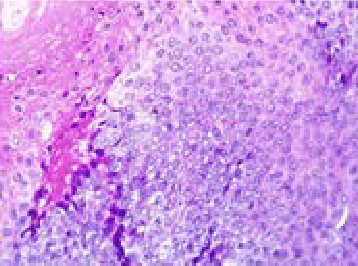

Multiple Pilomatricomas: A Case Report

Napasorn Phutong, Rachati Thongprayoon, Kongsak Loharamtaweethong and Nopadon Noppakun. 11(12): 18-21.